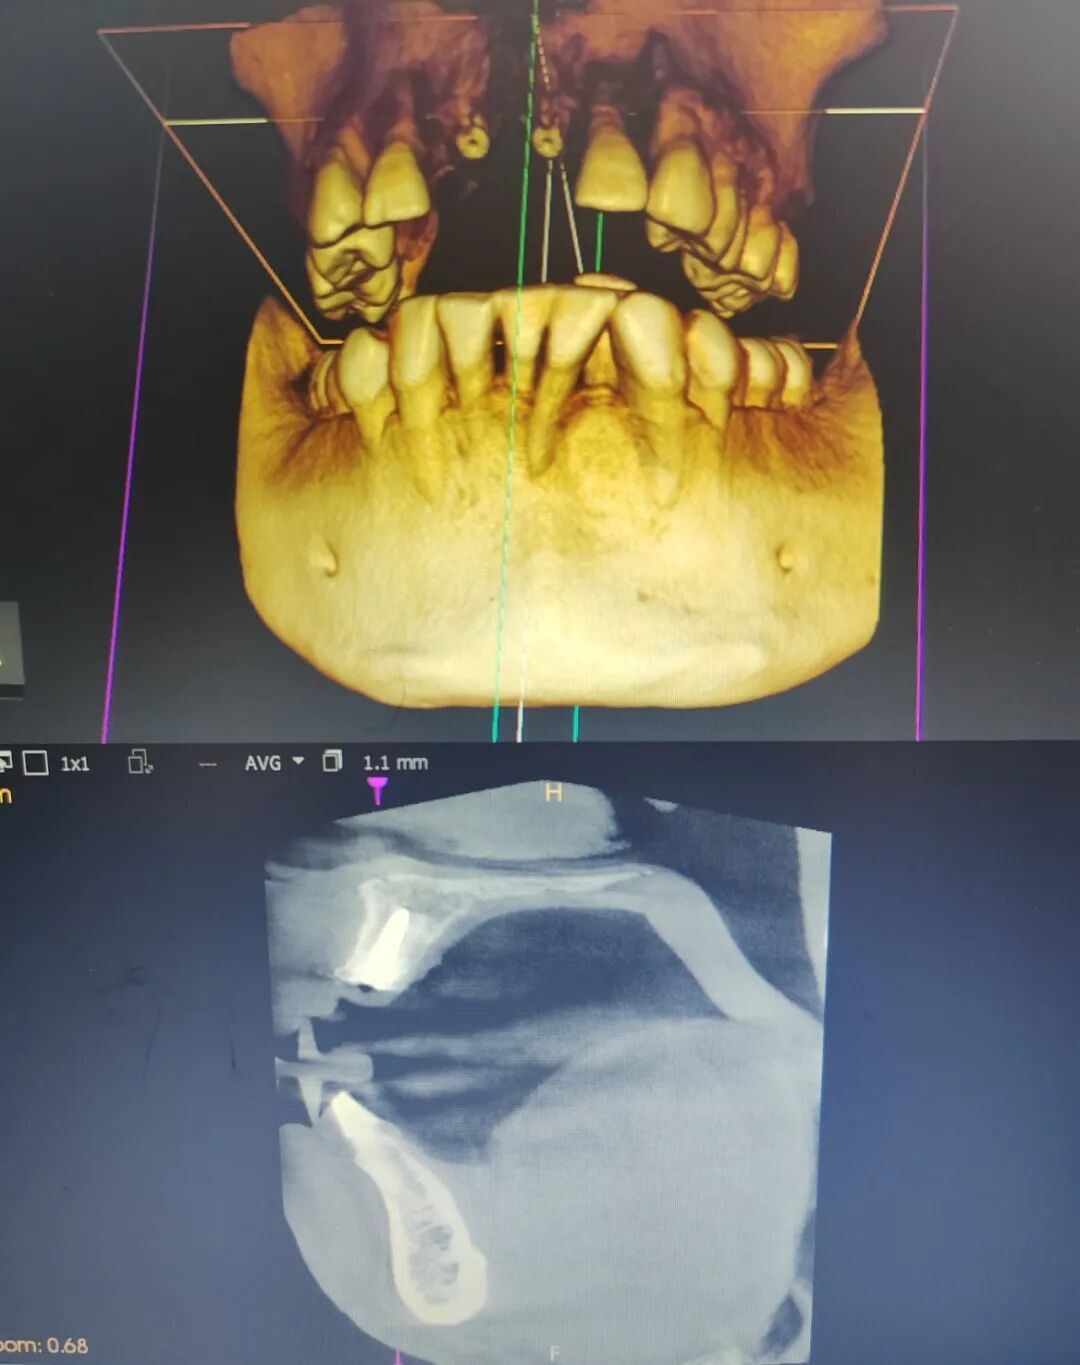

患者杨某,男,52岁,因上前牙缺失两年多,影响美观,就诊于我科决定行种植牙手术。术前CT检查,患者同意我科邰医生种植方案(数字化导板种植方案)。术中微创操作,术后无不良反应,整个疗程约一个小时,过程舒适、安全、精准,术后CT检查,种植体位置精准。